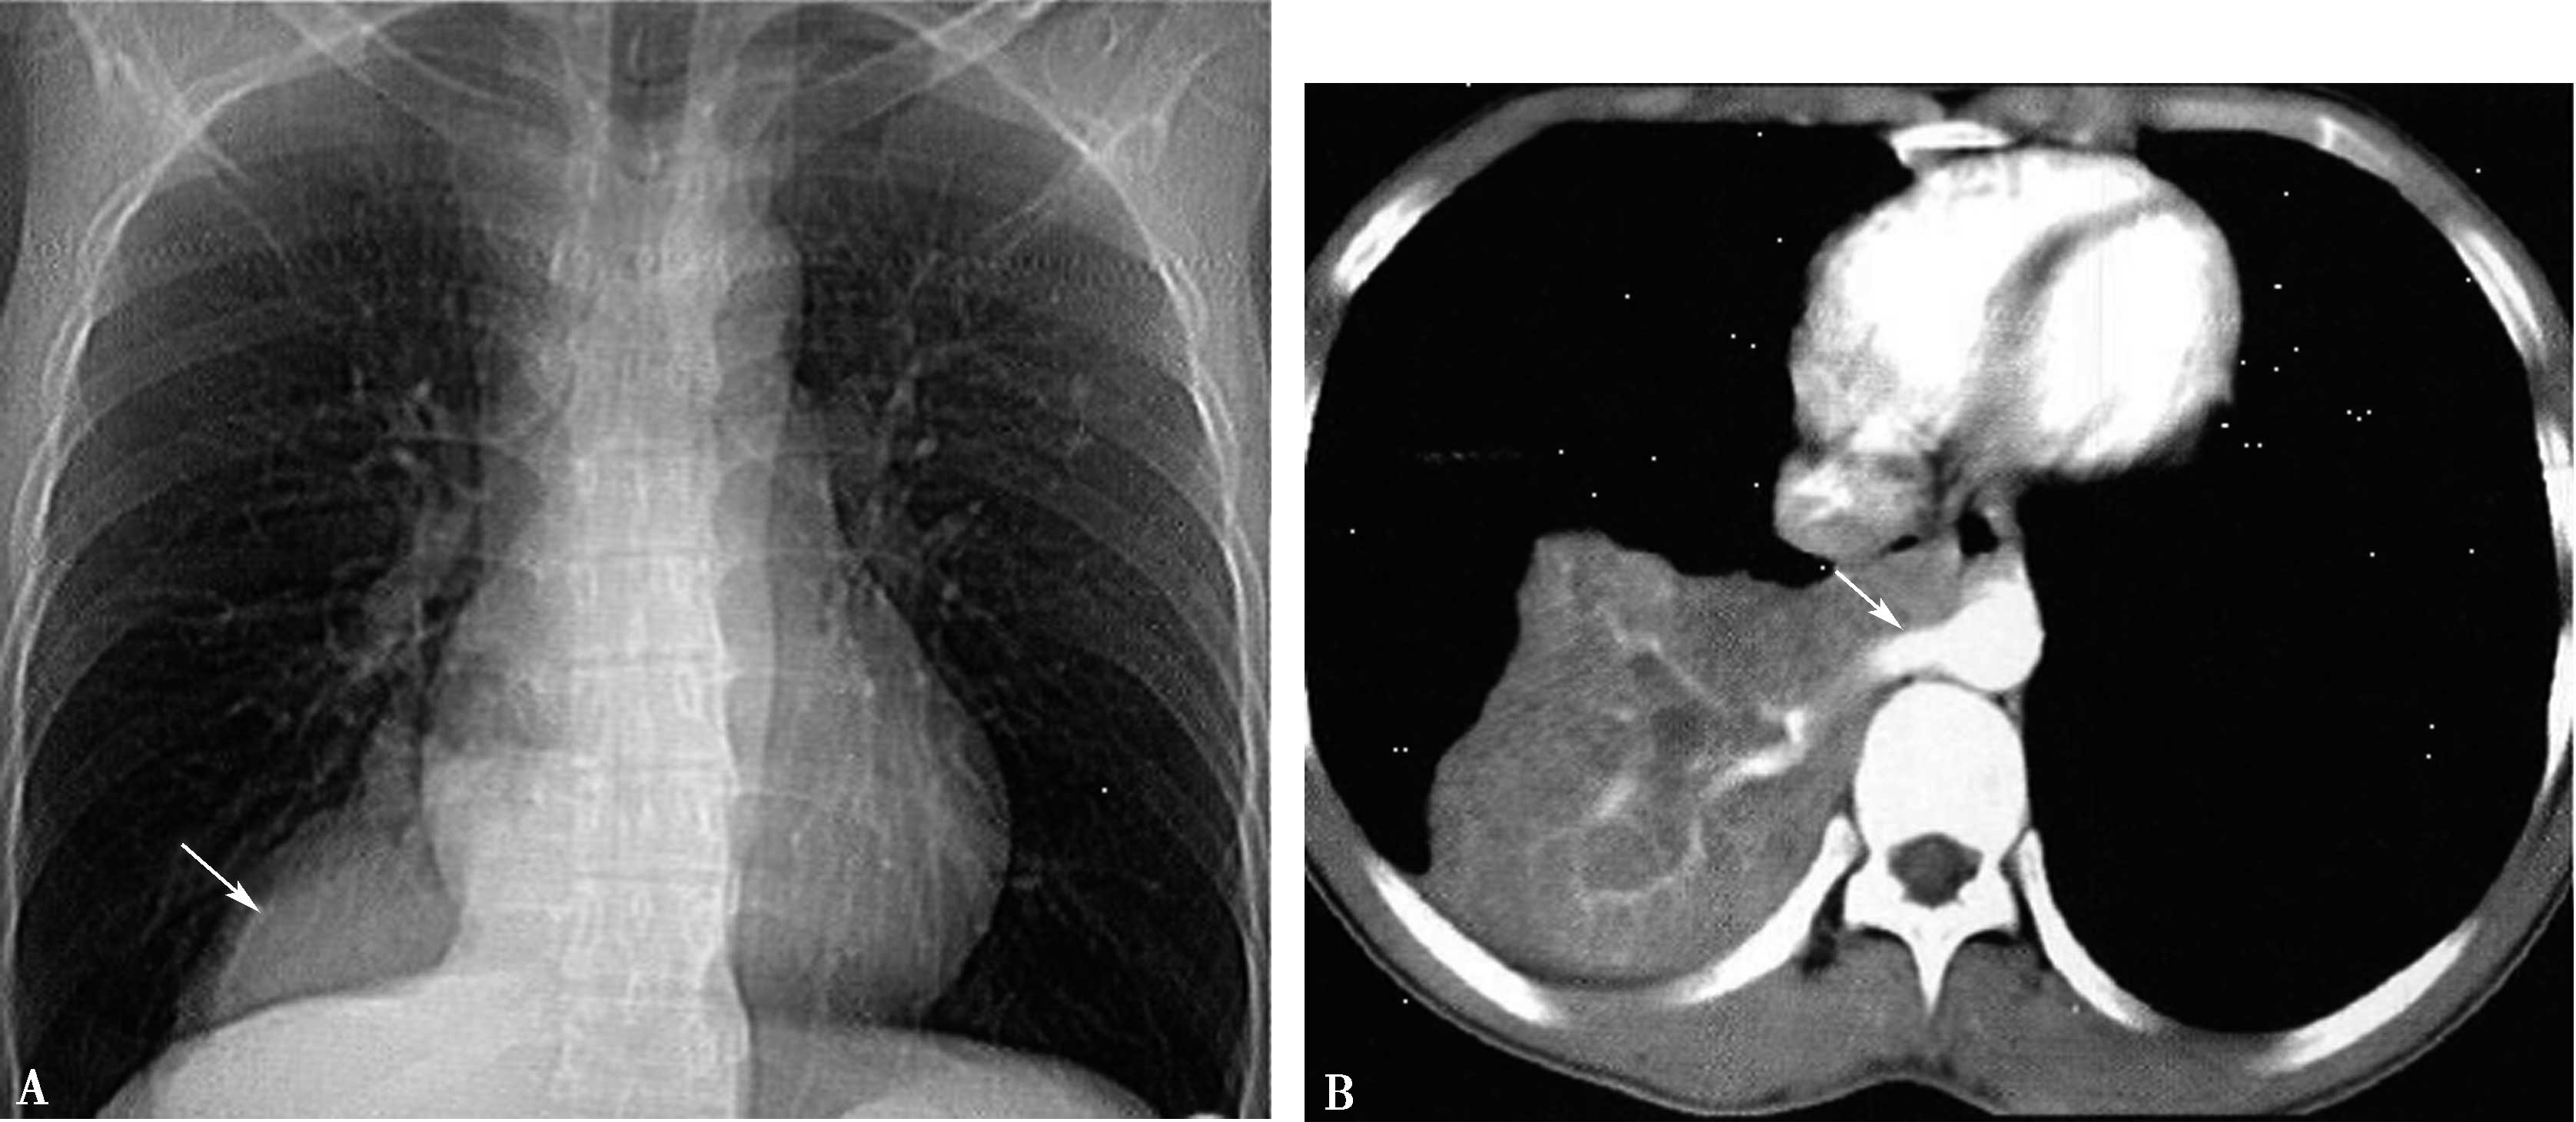

5.一期扫描 当ROI的CT值达到阈值时启动增强扫描程序。第一期扫描得到完整的肺静脉-左心房图像。如果达到诊断目的,可结束扫描(图8-1-11)。

图8-1-11 肺静脉CTA检查

A.上肺静脉(↑);B.下肺静脉(↑);C.肺静脉最大密度投影。LSPV:左上肺静脉;LIPV:左下肺静脉;RSPV:右上肺静脉;RIPV:右下肺静脉